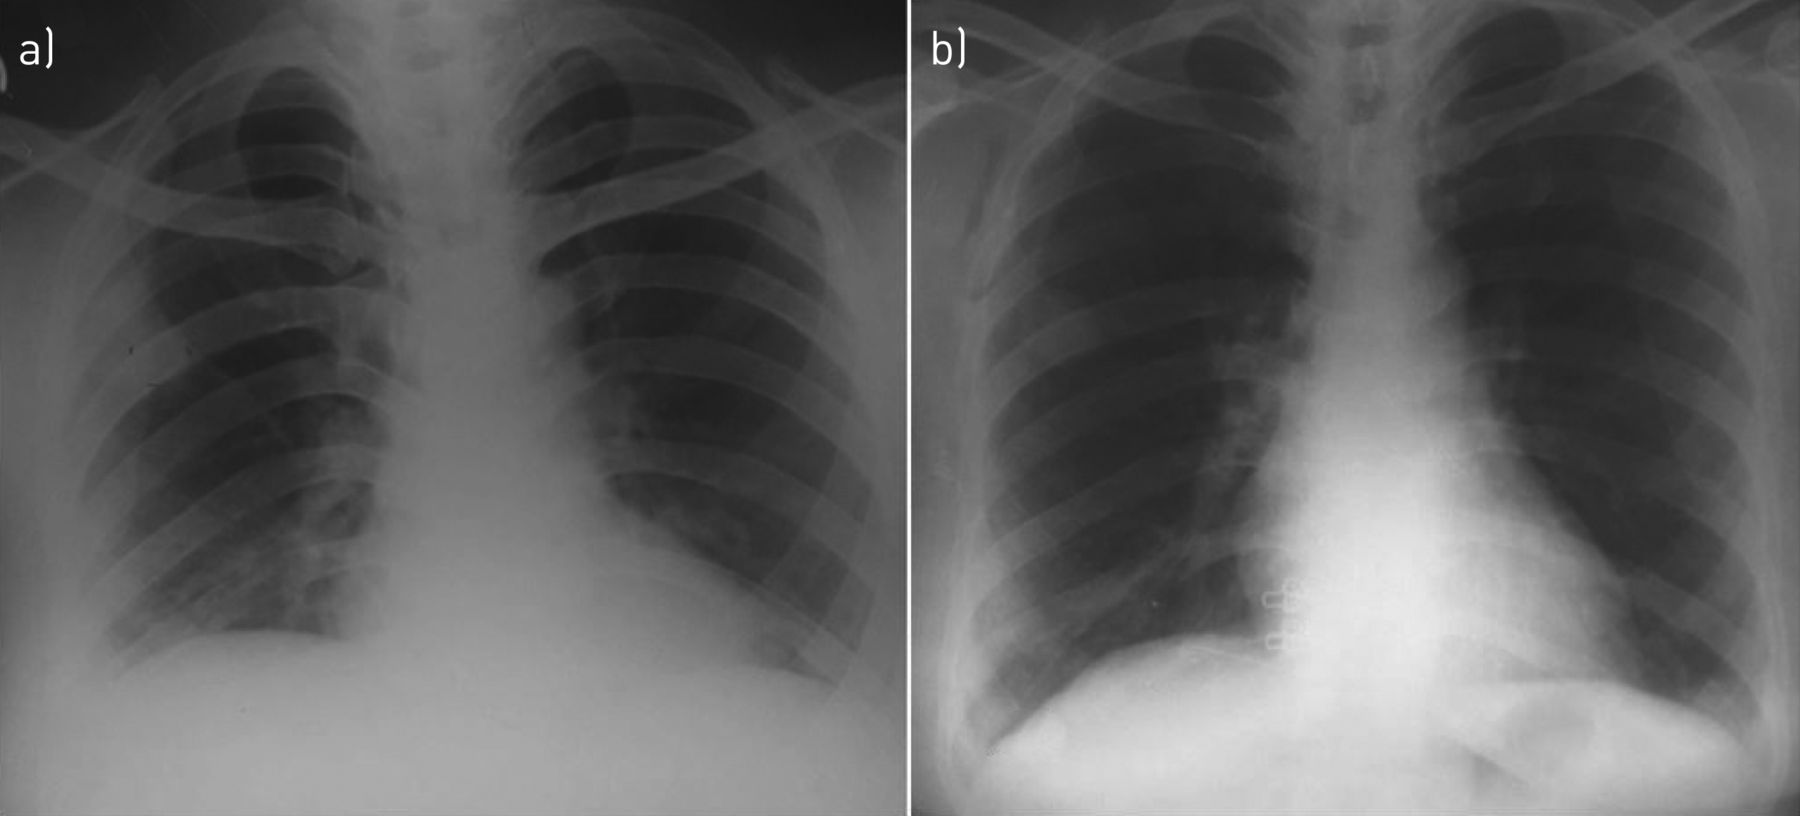

胸片肺结节影图片,肺癌x光片

胸片如何看肺炎,这篇文章帮你立刻入门!

一张胸片走江湖,这样的结节病你认出来了吗?